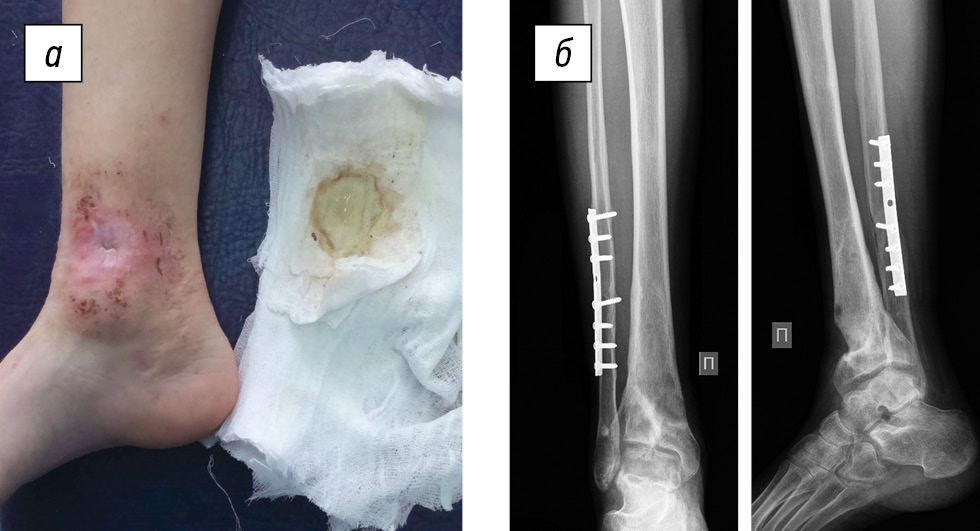

Status localis. The patient walks without aids and limps on the right limb. On the anterior inner surface of the leg in the lower third, a fistula of up to 5 mm in diameter was present, the skin around the fistula (up to 4 cm in diameter) was hyperemic and macerated, with cicatricial changes and scanty serous-purulent discharge (Fig. 4a). Palpation was moderately painful. Toe movement and sensitivity were preserved, and capillary response from the nail plates was brisk. The absolute length of the lower extremities was D < S per 1 cm. X-ray images of the right lower leg revealed a defect in the distal metaphysis of the tibia up to 1/2 the diameter, limited to a zone of sclerosis, proximal to the defect at the level of the metadiaphysis, a heterogeneous bone structure with small cysts, and undefined physeal zone. The fibula fracture consolidation with metal extracortical osteosynthesis was satisfactory (Fig. 4b).

Fig. 4. An 11-year-old female patient diagnosed with chronic post-traumatic osteomyelitis of the right tibia: a, appearance of the limb and the fistulous process; b, radiographs of the right ankle joint in two views

Fig. 6. Control radiographs after 6 months and integration of bone grafts without signs of an infectious–destructive process